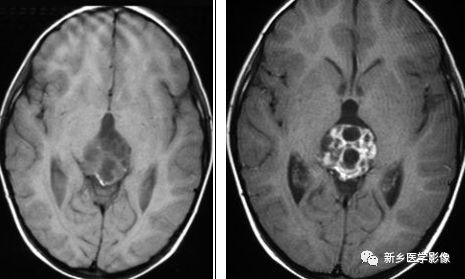

三侧性视网膜母细胞瘤

视网膜母细胞瘤是儿童眼内最常见的恶性肿瘤。该肿瘤通常在幼年期被诊断,通常在2岁以前。Calcification in the globe is seen on CT scans.CT扫描可观察到钙化,组织学检查中,钙化见于95%的视网膜母细胞瘤,这可解释CT上出现高钙化率的原因。三侧性视网膜母细胞瘤一词是指存在双侧视网膜母细胞瘤,伴有相关的中线原发性颅内肿瘤(通常在松果体区域,偶尔在鞍上或鞍旁区域)。约2-11%的双侧视网膜母细胞瘤患者存在这种共存的颅内肿瘤。颅内肿瘤被认为是不同于眼内肿瘤的病变,不是转移灶。通常眼内肿瘤和共存的颅内肿瘤之间通常存在潜伏期,通常约一年。

横断位T2WI示双侧眼球后方异常信号,横断位T1WI+C示异常强化,累及双侧眼球;矢状位T1WI+C示松果体区一强化肿物,符合松果体母细胞瘤,横断位CT示双侧眼球后方见钙化。